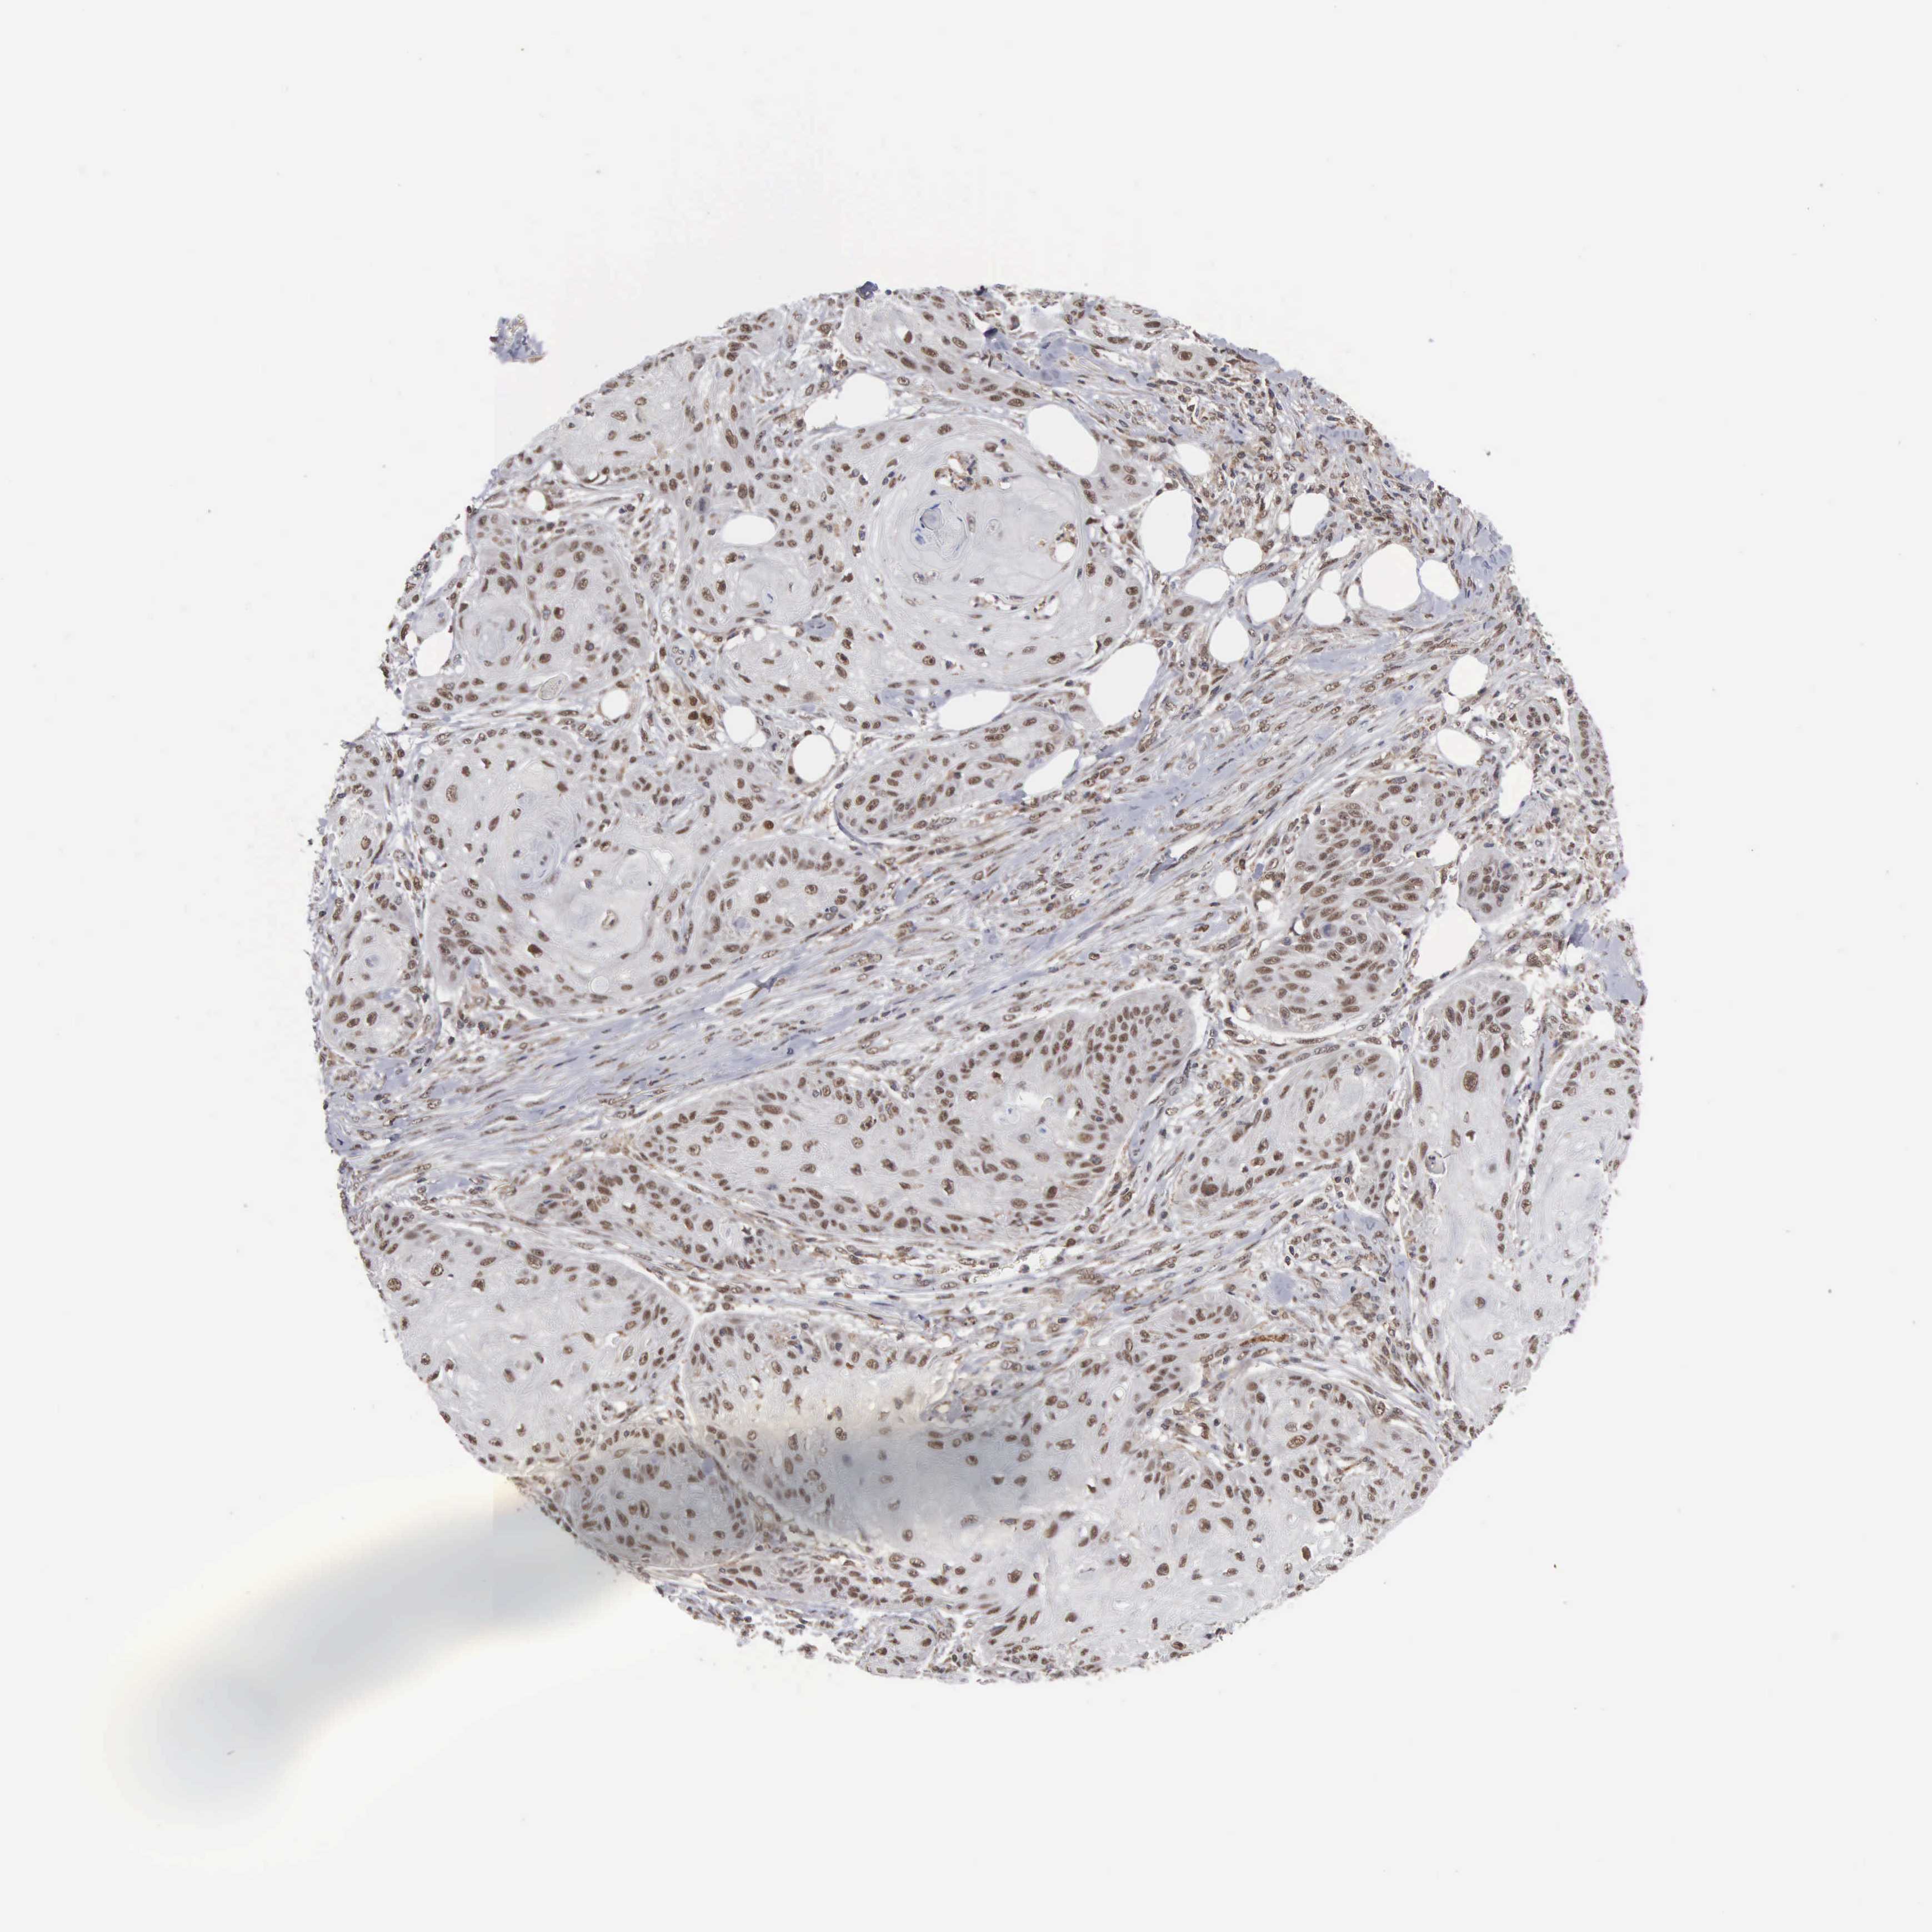

Basal cell and squamous cell cancer

SKIN CANCER - Protein expressioni

A mouse-over function shows sample information and annotation data. Click on an image to view it in a full screen mode. Samples can be filtered based on level of antibody staining by selecting one or several of the following categories: high, medium, low and not detected. The assay and annotation is described here.

Each image is clickable and will lead to virtual microscopy that enables deeper exploration of all samples and also displays staining intensity scores, fraction scores and subcellular localization as well as patient and tissue information for each sample.

Antibody HPA000943

Staining

High

Intensity

Strong

Quantity

>75%

Location

Nuclear

Squamous cell carcinoma, NOS